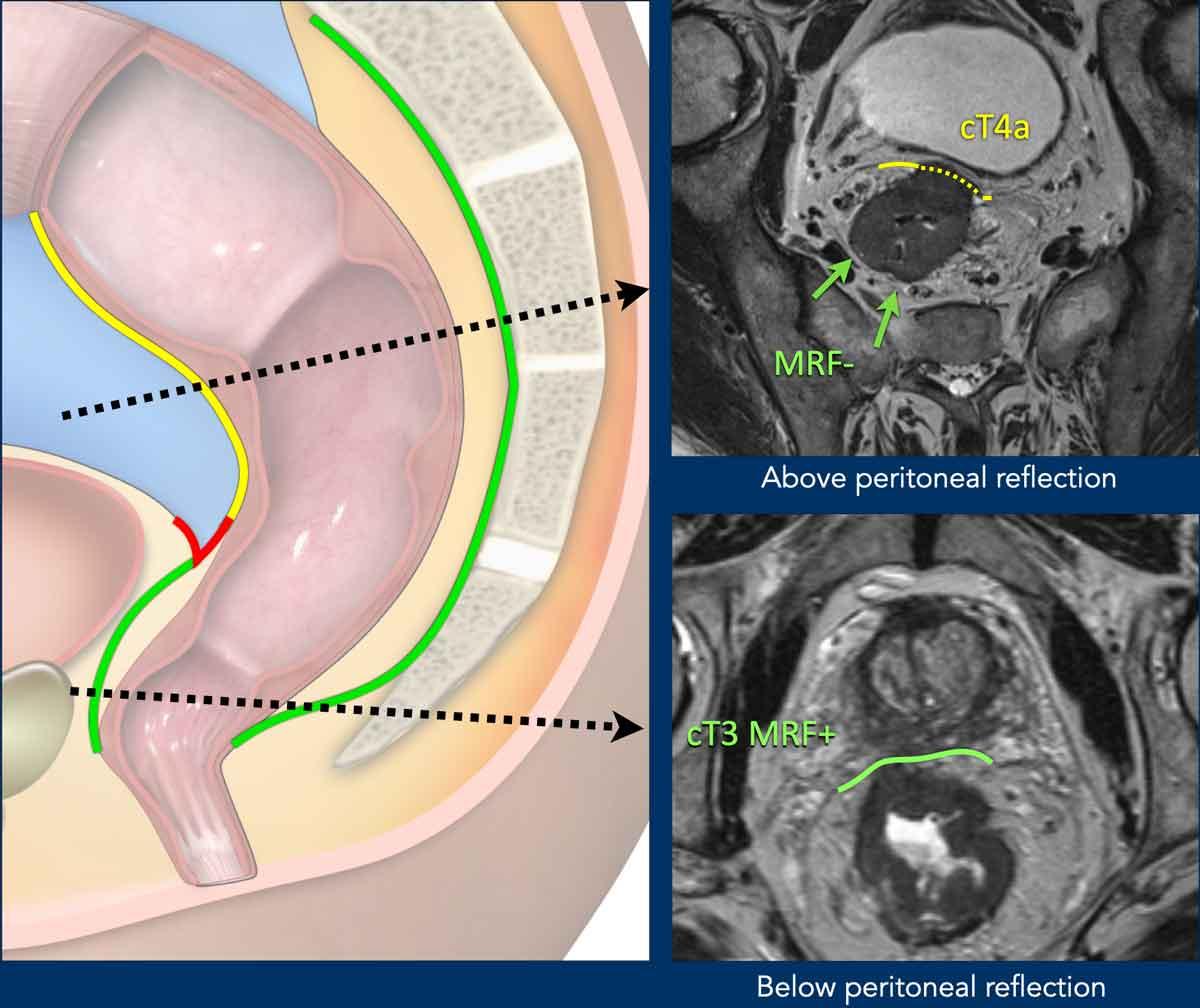

Mạc trực tràng giữa so với Phúc mạc

Vùng Giải Phẫu Bao Phủ:

- Trực tràng thấp:Được bao bọc hoàn toàn bởi mạc trực tràng (MRF, đường màu xanh lá).

- Trực tràng giữa:

- Sau/bên: Được bao phủ bởi MRF

- Phía trước: Được bao phủ bởi phúc mạc (đường đỏ, nếp phản chiếu phúc mạc)

- Trực tràng cao:Phúc mạc trải dài về phía trước và hai bên (đường màu vàng); MRF chỉ che phủ mạc treo trực tràng phía sau.

Ý nghĩa lâm sàng:

- Xâm lấn MRF:Được phân loại là T3 MRF+

- Xâm lấn phúc mạc:Nguy cơ lan rộng khối u vào phúc mạc; được phân giai đoạn là T4a

T4a Khối u

Mốc giải phẫu:

- Cáiphúc mạc phản chiếu trướcPhân định ranh giới chuyển tiếp giữa trực tràng không có phúc mạc và trực tràng có phúc mạc.

- Dưới nếp phúc mạc này, trực tràng hoàn toàn nằm ngoài phúc mạc.

Nhận dạng MRI:

- Trên hình ảnh T2 có trọng số theo mặt phẳng sagittal, phản chiếu phúc mạc xuất hiện như mộtgiảm tín hiệu, đường mảnh hình chữ V(mũi tên).

- Vị trí:

- Nam giới:Ngay phía trên túi tinh

- Nữ giới:Ở mức độ của túi cùng (túi Douglas)

Ý nghĩa phân giai đoạn:

- Xâm lấn phía trướccủa phản chiếu phúc mạc hoặc phúc mạc xác địnhBệnh T4a.

Cạm bẫy: Phân biệt MRF với Xâm lấn Phúc mạc trong Khối u Thành trước

Nguyên tắc chính:

- Ở phía trước, sự xâm lấn MRF chỉ có thể xảy ra trong các khối u nằm dưới nếp phúc mạc, được ghi nhận là T3 MRF+

Các khối u phía trước nằm trên mức phản chiếu phúc mạc mà xâm lấn phúc mạc nên được báo cáo là T4a MRF - Ở phía sau, MRF kéo dài trên mức phản chiếu phúc mạc. Sự xâm lấn đồng thời của MRF (phía sau) và phúc mạc (phía trước) có thể xảy ra, trường hợp này cần được báo cáo là T4a MRF+

Ví dụ về Hình ảnh

cT4a MRF–I need the actual HTML text fragment to translate. You’ve only provided a description “(Upper Image):” but no HTML content to translate.

Please provide the HTML text fragment you’d like me to translate from English to Vietnamese.

- Khối u trực tràng trên, trên nếp phúc mạc

- Liên quan phúc mạc (đường vàng đứt nét)

- Không có sự tham gia của MRF

cT3 MRF+(Hình ảnh phía dưới):

- Khối u trực tràng đoạn xa, dưới mức phúc mạc phản chiếu

- Liên quan đến MRF phía trước (đường màu xanh lá)

- Không có sự xâm lấn phúc mạc

Khối u cT4a MRF+

Khối u trực tràng gần này cho thấy sự xâm lấn kết hợp:

- Phía trước: Xâm lấn phúc mạc (T4a)

- Sau: Xâm lấn mạc trực tràng (MRF) (MRF+)